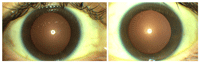

Mujer de 44 años con antecedentes personales de hepatitis C, acude por uveítis anterior aguda bilateral; la agudeza visual bilateral es de 0,5.En la biomicroscopía destaca Tyndall de 5 células por campo, sin sinequias y con depósitos pigmentarios en cristaloides anterior bilateral (Figura 1).

Figura 1. Biomicroscopia: ausencia de sinequias posteriores sin precipitados queráticos tras la desaparición del Tyndall.

Tres semanas más tarde debuta con uveítis anterior aguda unilateral, no fibrinoide, sinequiante en su ojo izquierdo (OI) (Figura 5). Se realiza detección inmunológica e infecciosa, siendo todo ello negativo.

Figura 5. Biomicroscopía ojo izquierdo 1 semana después del debut, se observa que ha existido actividad previa, depósitos pigmentarios sobre la cápsula anterior del cristalino y sinequias que han roto.